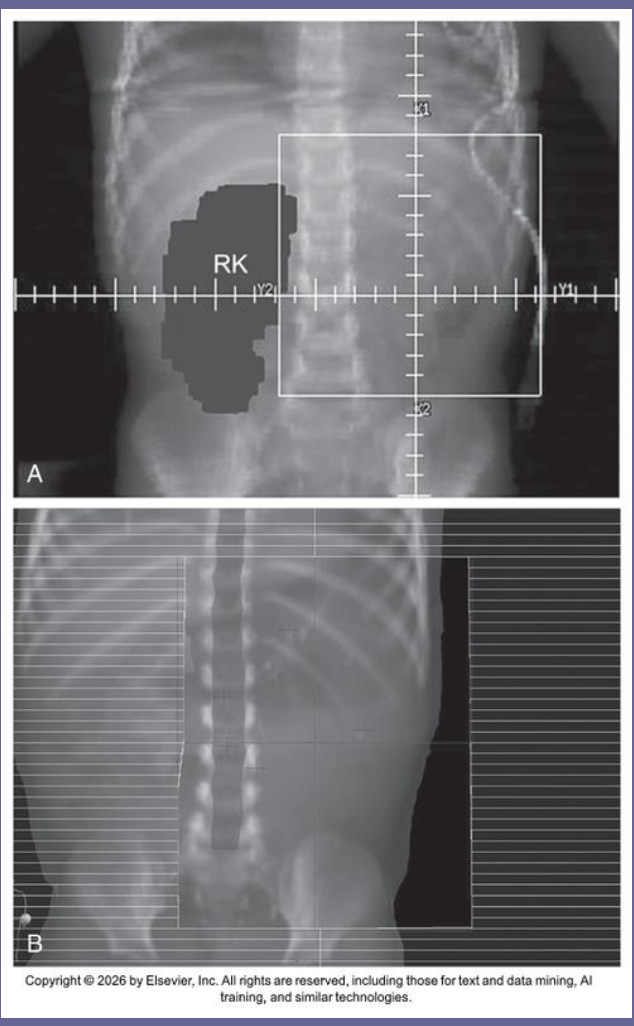

What is Wilms tumor?

malignant tumor of the kidney (one/both)

What is another name for Wilms tumor?

nephroblastoma

Median age of occurance for Wilms tumor?

ages 3-4 years old

Signs and symptoms of Wilms tumor?

typically painless abdominal mass

patients typically don’t appear ill looking

How does Wilms tumor grow?

grows rapidly and tends to rupture into abdomen

Common site for mets with Wilms tumor?

Lung

3 Unfavorable histologies for Wilms tumor?

Anaplastic

Clear cell sarcoma

Rhabdoid tumor (poor prognosis)

*excellent prognosis for other histologies*

Staging system for Wilms tumor?

National Wilms Tumor Study Group (NWTS) staging system

3 Treatments for Wilms tumor

nephrectomy

chemo

radiation (3D conformal with MLCs to block healthy kidney)